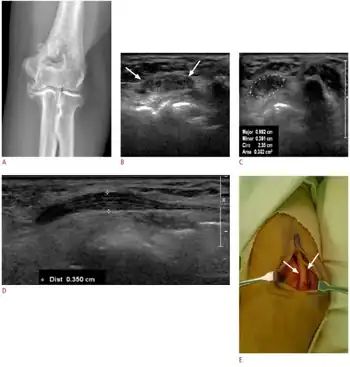

A nerve may be compressed by prolonged or repeated external force, such as sitting with one's arm over the back of a chair (radial nerve), frequently resting one's elbows on a table (ulnar nerve), or an ill-fitting cast or brace on the leg (peroneal nerve). Part of the patient's body can cause the compression and the term entrapment neuropathy is used particularly in this situation. The offending structure may be a well-defined lesion such as a tumour (for example a lipoma, neurofibroma or metastasis), a ganglion cyst or a haematoma. Alternatively, there may be expansion of the tissues around a nerve in a space where there is little room for this to occur, as is often the case in carpal tunnel syndrome. This may be due to weight gain or peripheral oedema (especially in pregnancy), or to a specific condition such as acromegaly, hypothyroidism or scleroderma and psoriasis.